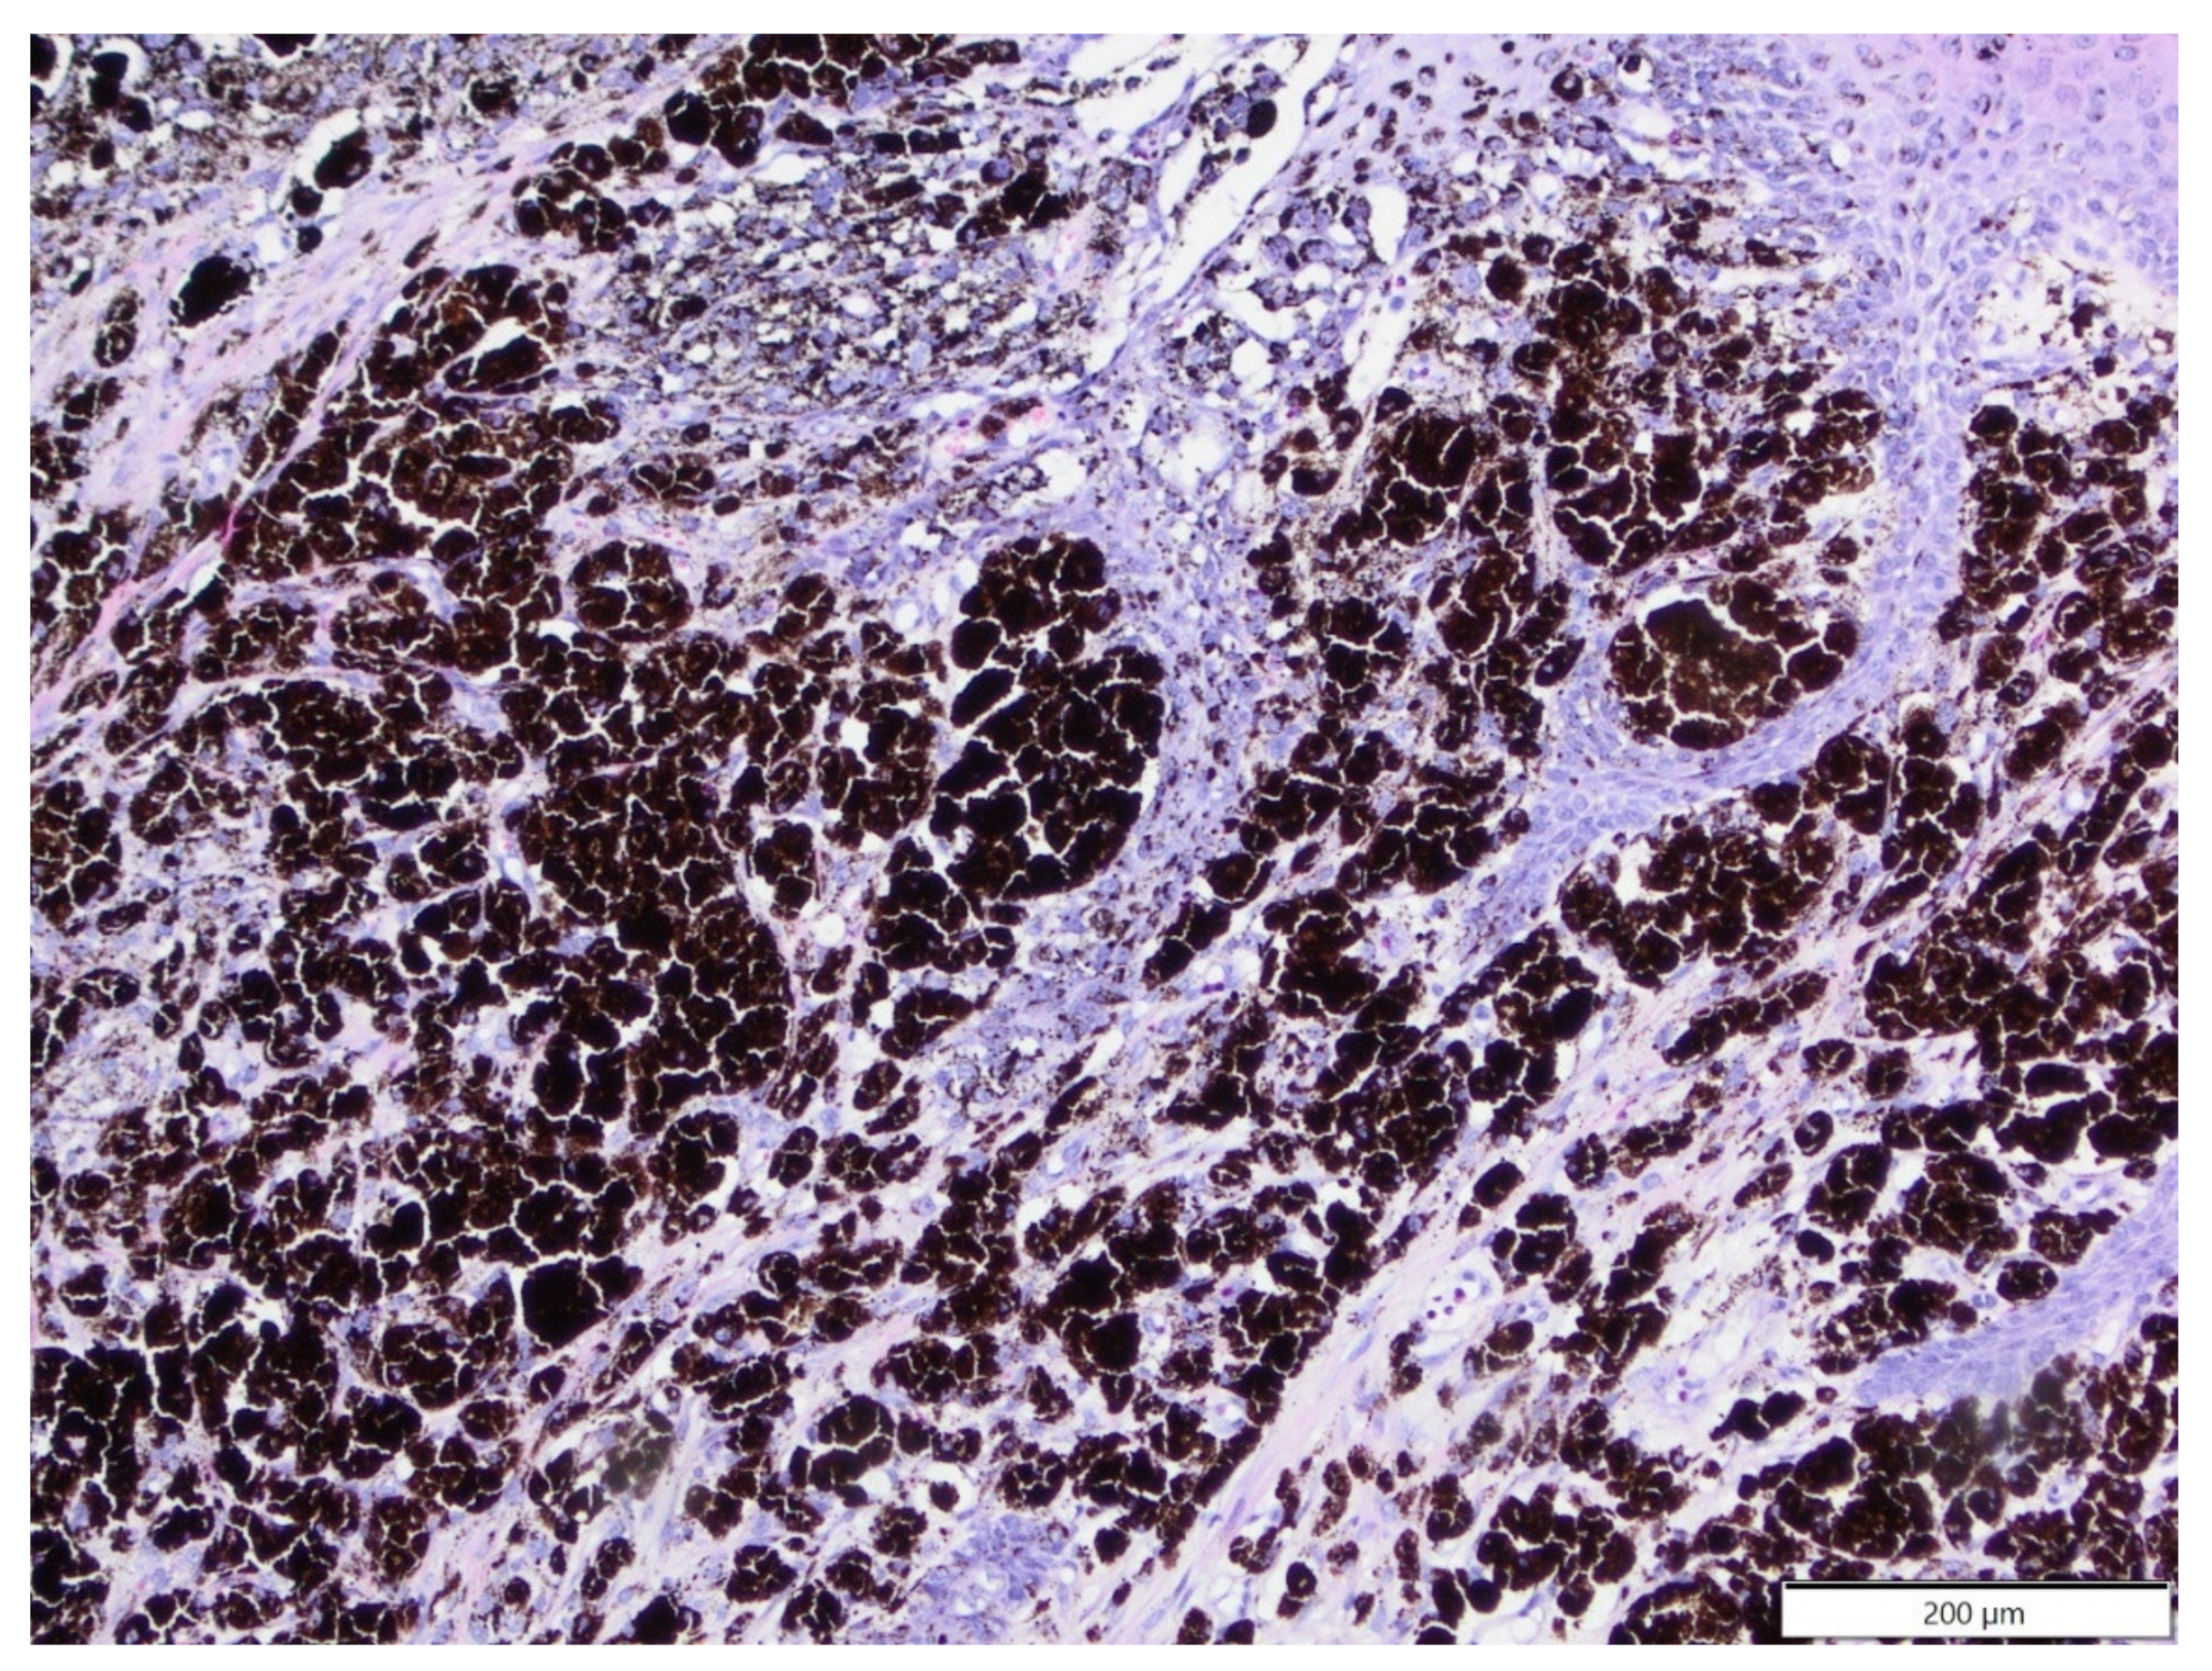

Figure 6.

Histiocytic sarcoma, forelimb, African pygmy hedgehog. Pleomorphic tumour cells show high anisocytosis and anisokaryosis. Nuclei are large with marginated chromatin and distinct, single nucleoli. HE. Inset: tumour cells show expression of Iba-1. IHC.